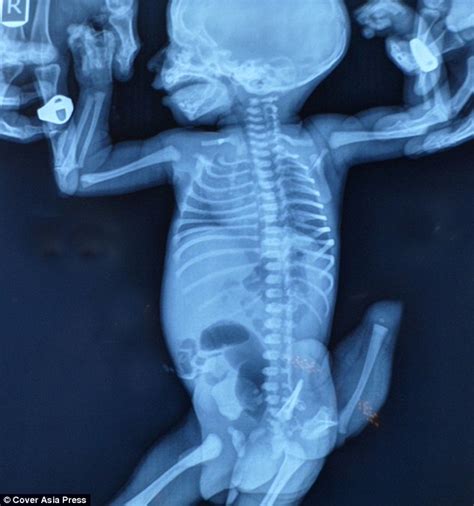

During early human embryonic development, every fetus temporarily develops a tail-like structure between the fourth and eighth weeks of gestation. Typically, this embryonic tail naturally regresses and transforms into the coccyx (tailbone) by the eighth week of pregnancy. However, in extremely rare instances, this tail fails to disappear completely, resulting in a genuine human tail at birth.

| Composition | Soft tissue including muscles, blood vessels, and nerves (no bone or cartilage) |

Contrary to historical beliefs that considered human tails merely evolutionary curiosities, modern medical research suggests these appendages might indicate underlying neurological conditions. Approximately 50% of cases are associated with spinal dysraphism or other neurological abnormalities. Medical professionals now recommend comprehensive neurological evaluations and imaging for babies born with tail-like structures.